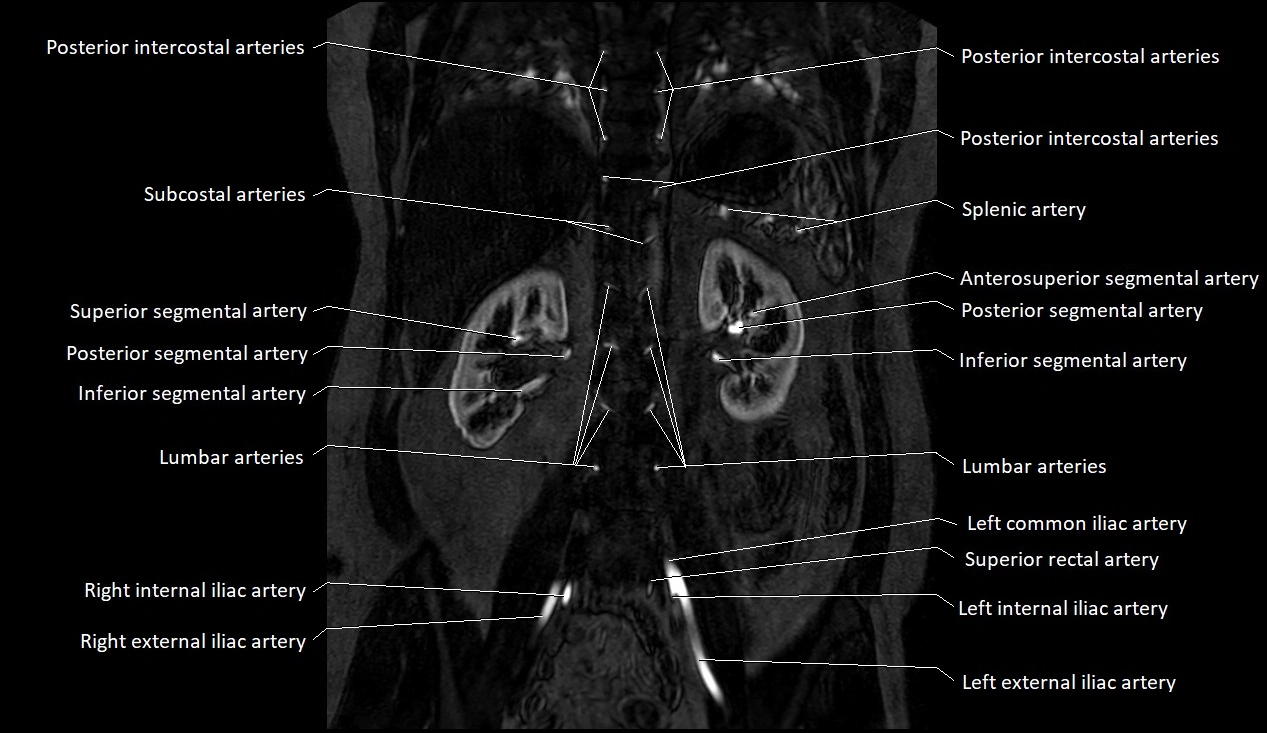

MRI images

image